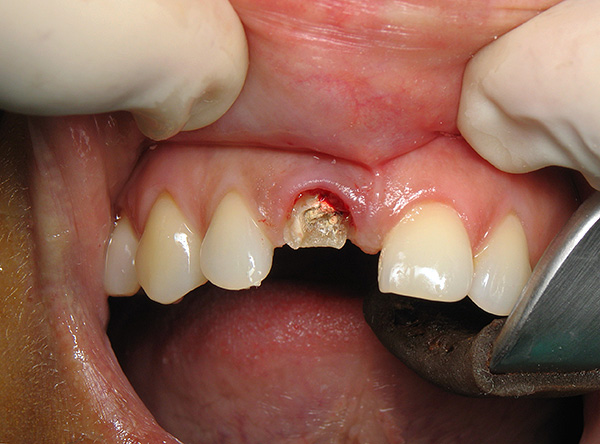

A foto abaixo mostra um exemplo de um dente da frente quebrado a ser removido:

A natureza da preparação depende dos recursos de manipulação futura (com ou sem anestesia, com ou sem sedação), mas as etapas mais básicas incluem: